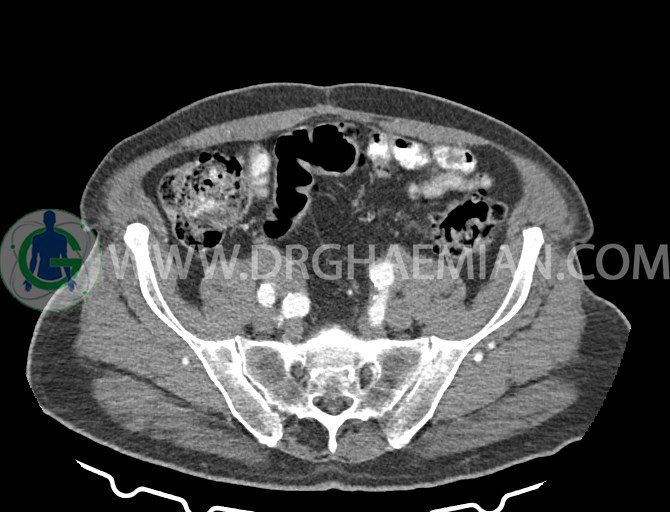

سی تی اسکن لگن یکی از روش های تصویربرداری با سی تی اسکن است. این روش با استفاده از تشعشعات تصاویر عرضی از ناحیه شکمی ایجاد میکند. در این کیس ديورتيكولوزيس، کیست های کورتیکال در هر دو کلیه، لنفادنوپاتی، کلسیفیکاسیون دیواره آئورت و شریان ایلیاک، تغییرات DJD ناحیه توراکولومبار و پروستات بزرگتر از عادی دیده می شود.

– کلسيفيکاسيون ديواره آئورت و شريان ها ايلياک همراه با نشانه هاي ترومبوز مورال در بيفورکاسيون ائورت با امتداد به پروگزيمال هاي شريان هاي ايلياک

لنفادنوپاتي به ابعاد mm 22 x 25 مجاور شريان ايلياک خارجي چپ و به ابعاد mm 17 x 28 مجاور شريان ايلياک خارجي راست